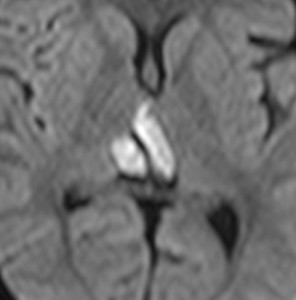

MRIです

左の拡散強調画像で高信号となり類表皮のう胞 epidermoid cyst あるいは類皮のう胞 dermoid cyst の診断です。しかし右のT2強調画像では左後方に違う信号の腫瘍塊があります。

ガドリニウム増強像です。類皮のう胞(成熟奇形腫 mature teratoma)との混合性胚細胞腫瘍を強く疑う所見です。